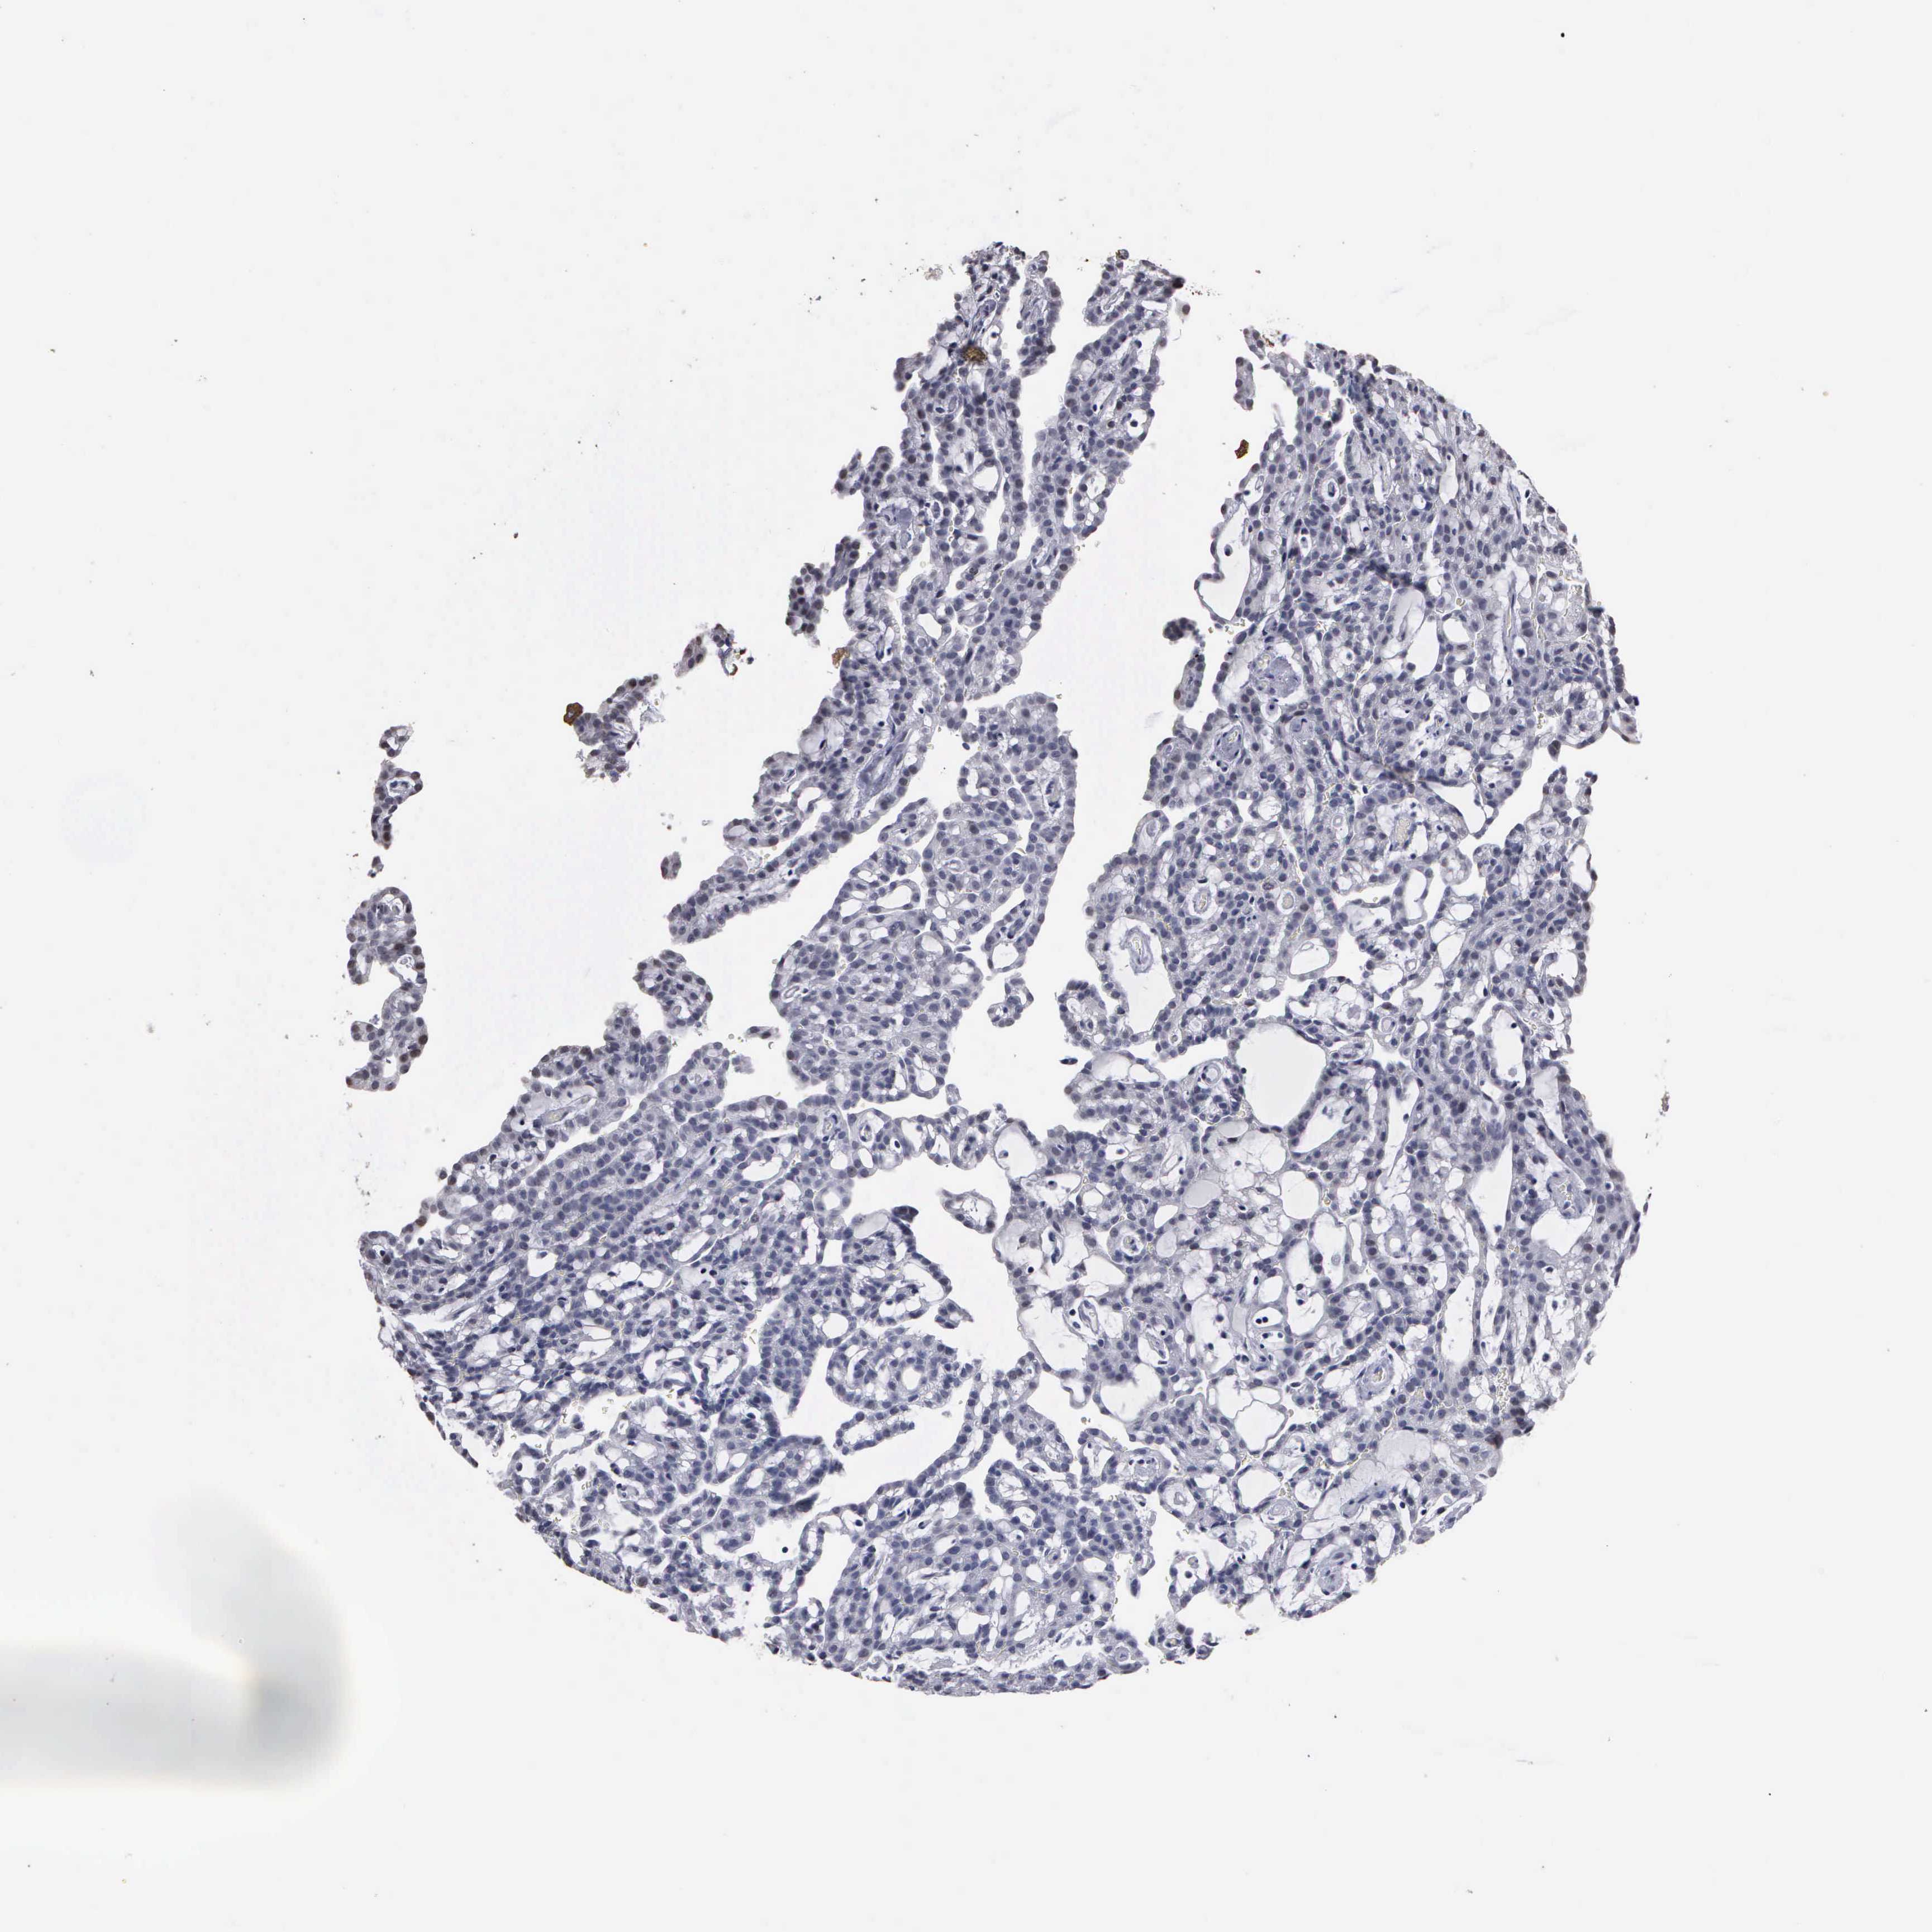

KIDNEY RENAL CLEAR CELL CARCINOMA (VALIDATION) - Interactive survival scatter ploti

The Survival Scatter plot shows the clinical status (i.e. dead or alive) for all individuals in the patient cohort, based on the same data that underlies the corresponding Kaplan-Meier plots. Patients that are alive at last time for follow-up are shown in blue and patients who have died during the study are shown in red.

& Survival analysisi

Kaplan-Meier plots summarize results from analysis of correlation between mRNA expression level and patient survival. Patients were divided based on level of expression into one of the two groups "low" (under cut off) or "high" (over cut off). X-axis shows time for survival (years) and y-axis shows the probability of survival, where 1.0 corresponds to 100 percent.

UPB1 is validated prognostic, high expression is favorable in Kidney Renal Clear Cell Carcinoma (validation)

: 4.79

Average pTPM 8.8

Number of samples 100